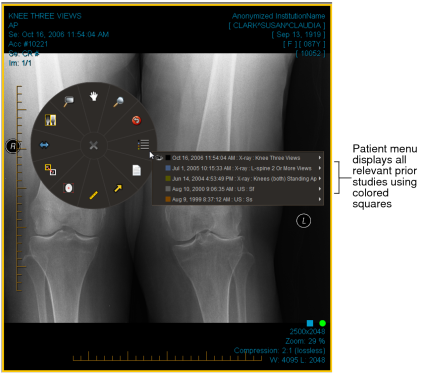

The InteleViewer elements that use a color scheme are the Thumbnail strip, Studies list, viewport text overlays, Patient menu, and the Comparison list in the Protocol Preview pane.

Black represents the current study and dark blue represents the most recent prior study. Prior studies are represented by a repeating sequence of five colors.